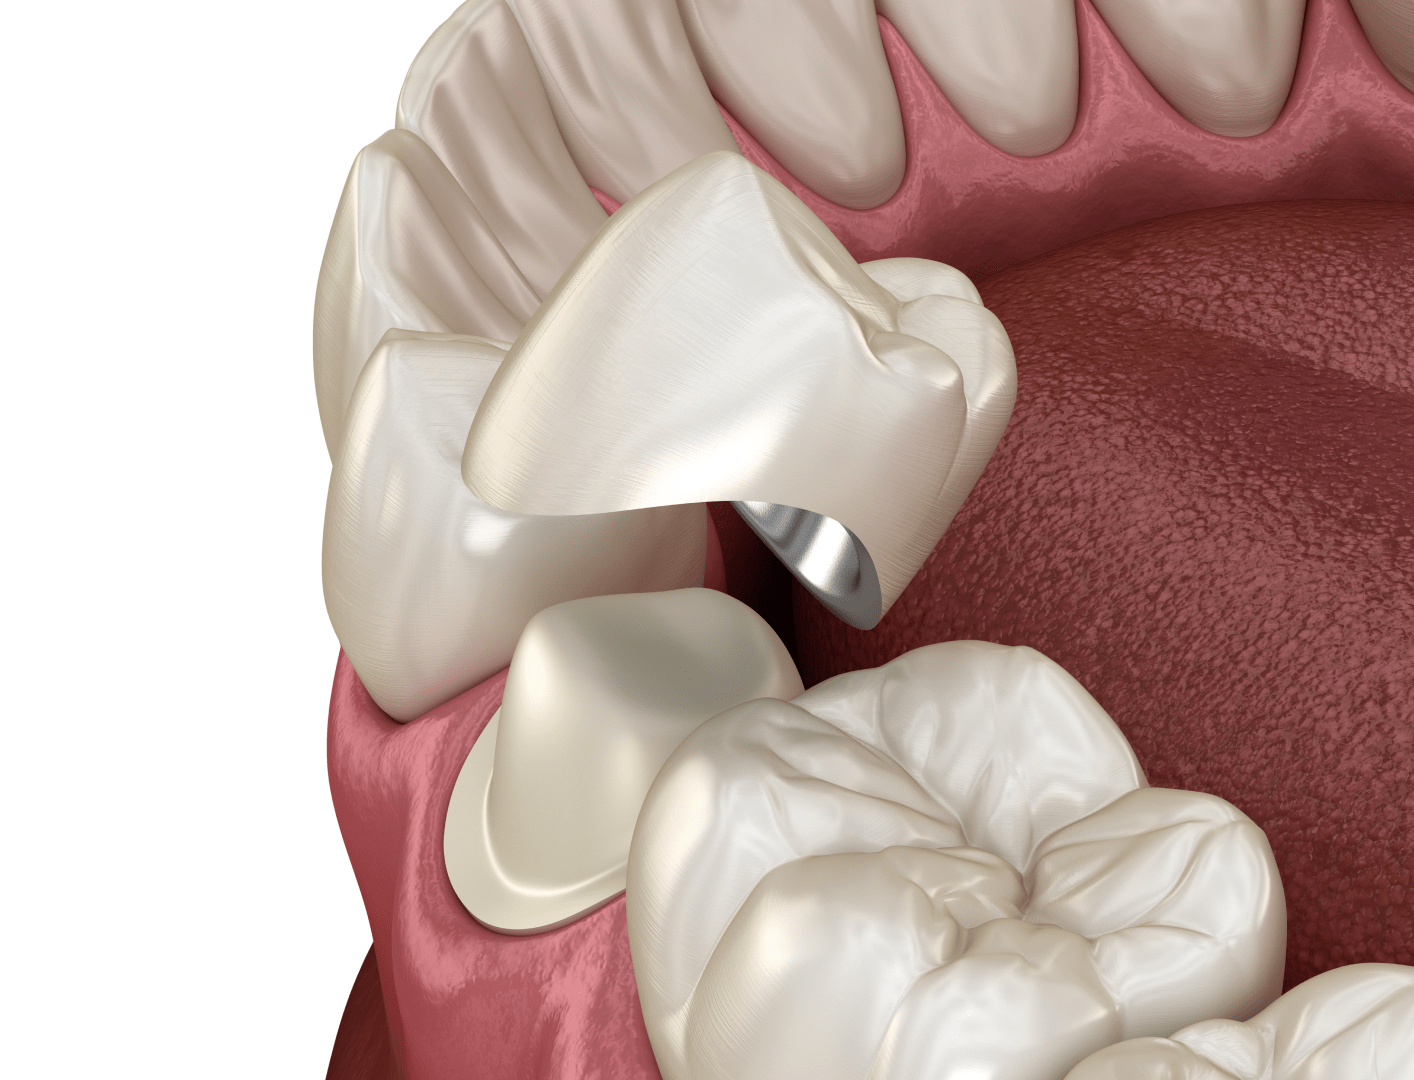

Втрата або значне пошкодження зуба — поширена проблема, з якою стикаються багато людей. Однак у сучасній стоматології існують ефективні способи її вирішення. Одним із таких методів є встановлення металокерамічних коронок на зруйнований зуб або на імплант (у разі його відсутності).

Металокерамічні коронки — це протези, що складаються з міцного металевого каркаса та керамічного покриття. Така конструкція дозволяє відновити анатомічну форму зуба, його жувальну функцію та естетику. Завдяки керамічному шару коронка виглядає максимально природно, тому її зовнішній вигляд майже неможливо відрізнити від натурального зуба.

Металокерамічна коронка — це незнімний зубний протез, який встановлюють на попередньо підготовлений (обточений) зуб або фіксують на зубний імплант у разі відсутності природного кореня. Така конструкція використовується для відновлення форми, функції та естетики сильно пошкоджених або втрачених зубних одиниць.

Коронка з металокераміки має двошарову конструкцію. Основою протеза є міцний металевий каркас, який виготовляють зі спеціальних стоматологічних сплавів, наприклад кобальто-хромового або інших біосумісних матеріалів. Саме каркас надає коронці високу міцність і здатність витримувати значні жувальні навантаження.

Зовнішня частина коронки покривається шаром стоматологічної кераміки. Вона відтворює природний колір, прозорість і форму зубної емалі, завдяки чому конструкція виглядає максимально натурально. Надійне з’єднання металевого каркаса та керамічного покриття досягається під час термічної обробки у зуботехнічній печі, де матеріали поєднуються на молекулярному рівні.